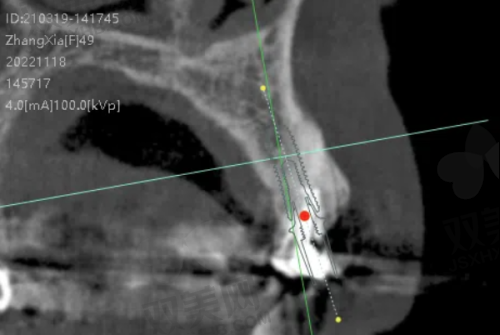

在进行一颗种植牙治疗前,患者需要进行全方面的口腔检查和评估。医生会通过口腔X光、CT等检查手段,了解患者的牙槽骨密度、高度、宽度等情况,同时评估患者的全身健康状况,排除手术禁忌证。根据检查结果,医生会为患者制定个性化的种植方案。

种植体植入手术

在局部麻醉下,医生会在患者的牙槽骨上制备一个合适的种植窝,然后将种植体植入其中。手术过程中,医生会严格遵循无菌操作原则,确保手术的安心性。植入种植体后,患者需要等待一段时间,让种植体与牙槽骨形成骨结合,这个过程一般需要3 - 6个月。